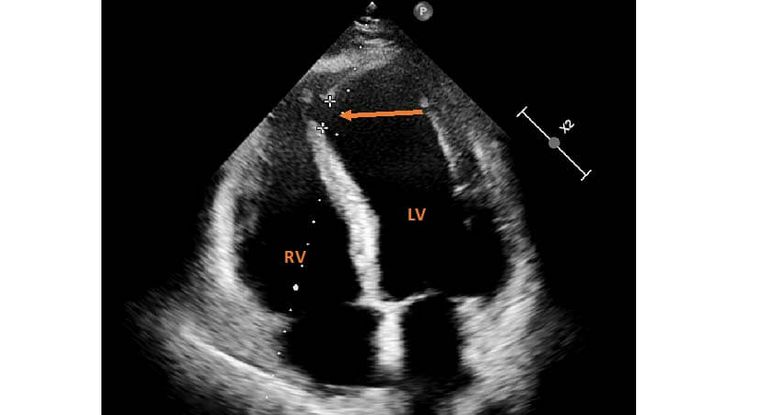

Ventrikelseptumdefekt (VSD) Ventrikelseptumdefekt (VSD) Ein Ventrikelseptumdefekt (VSD) ist eine angeborene Verbindung (Defekt) zwischen der linken und rechten Herzkammer. Der

Der Ventrikelseptumdefekt (VSD) ist ein Loch in der Herzscheidewand zwischen den Herzkammern. Die Scheidewand besteht aus einem membranösen und einem muskulären Herzgeräusche Quellen Leitlinien Deutsche Gesellschaft für Pädiatrische Kardiologie. S2k-Leitlinie Abklärung eines Herzgeräusches im Kindes- und Jugendalter. AWMF-Leitlinie 023